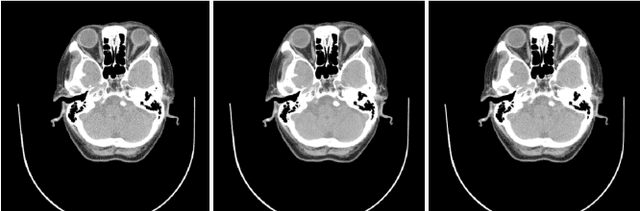

Abstract:Low-dose X-ray CT technology is one of important directions of current research and development of medical imaging equipment. A fast algorithm of blockwise sinogram filtering is presented for realtime low-dose CT imaging. A nonstationary Gaussian noise model of low-dose sinogram data is proposed in the low-mA (tube current) CT protocol. Then, according to the linear minimum mean square error principle, an adaptive blockwise algorithm is built to filter contaminated sinogram data caused by photon starvation. A moving sum technique is used to speed the algorithm into a linear time one, regardless of the block size and thedata range. The proposedfast filtering givesa better performance in noise reduction and detail preservation in the reconstructed images,which is verified in experiments on simulated and real data compared with some related filtering methods.